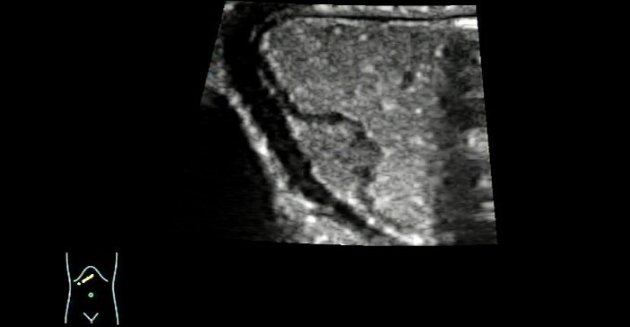

The patient underwent ultrasound examination after drinking 500 mL of contrast agent (instant gastrointestinal ultrasound aid) in a fasted state. The gastric wall featured a clear well-layered structure and a lack of mucosal smoothness, and a moderately hypoechoic mass of about 1.36 cm × 0.87 cm in size was detected in the submucosal layer of the lesser curvature of the gastric antrum. The mass was ovoid with clear margins, a broad base, and a continuous mucosal surface.

Moreover, a shallow depression was spotted in the center of the mass, with uneven echogenicity inside the mass (Figure 3).

Color Doppler Flow Imaging (CDFI) revealed that a signal indicative of a thin stream of blood flow could be identified near the base of the mass. (Figure 4). Ultrasound indicated a submucosal occupying lesion in the stomach, and ectopic pancreas was suspected.

Figure 3. Contrast-enhanced ultrasound imaging of the gastric window demonstrating heterogeneity within the mass.

Figure 4. CDFI: Thin stream of blood flow identified near the base of the mass.